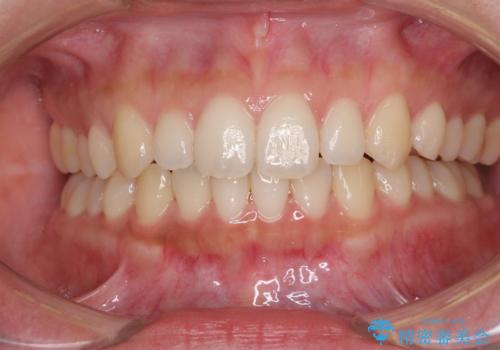

海外勤務中でも矯正治療 インビザラインによる軽度叢生改善

- 前歯のデコボコを気にして来院された患者様です。

通常であれば半年から10ヶ月程度で終了する歯並びでしたが、海外に長期出張することになったため、1年10ヶ月の期間を要しました。